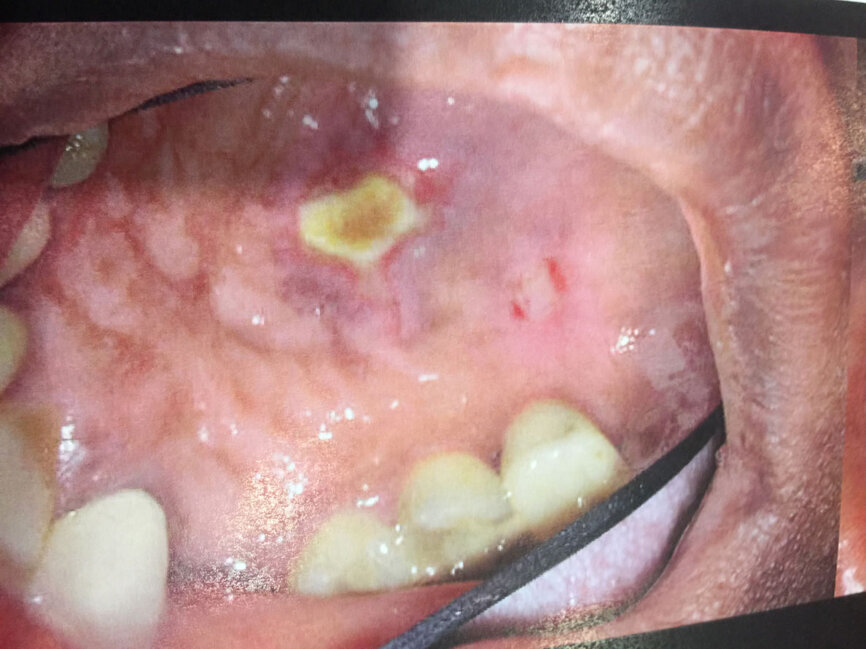

All procedures must be carefully pre planned. Such treatment planning includes performing high-level imaging and a thorough clinical examination to determine a definitive diagnosis. Pre-operative treatment planning includes informed consent, assurance of restorability, profound pain control (local anesthesia), visualization and magnification (surgical microscopes), instrumentation (stainless and nickel titanium), irrigation and disinfection protocols, obturation and coronal seal strategies prior to endodontic access. A lack of treatment planning strategies is the harbinger of endodontic misadventure (Figs. 1-3).

Fig. 1: Sodium hypochlorite accident post operatively, extra oral. (All images provided by Brett Gilbert, DDS, and Richard Mounce, DDS)

Fig. 2: Sodium hypochlorite accident approximately five months post op, intra oral (different case than that shown in Fig. 1).